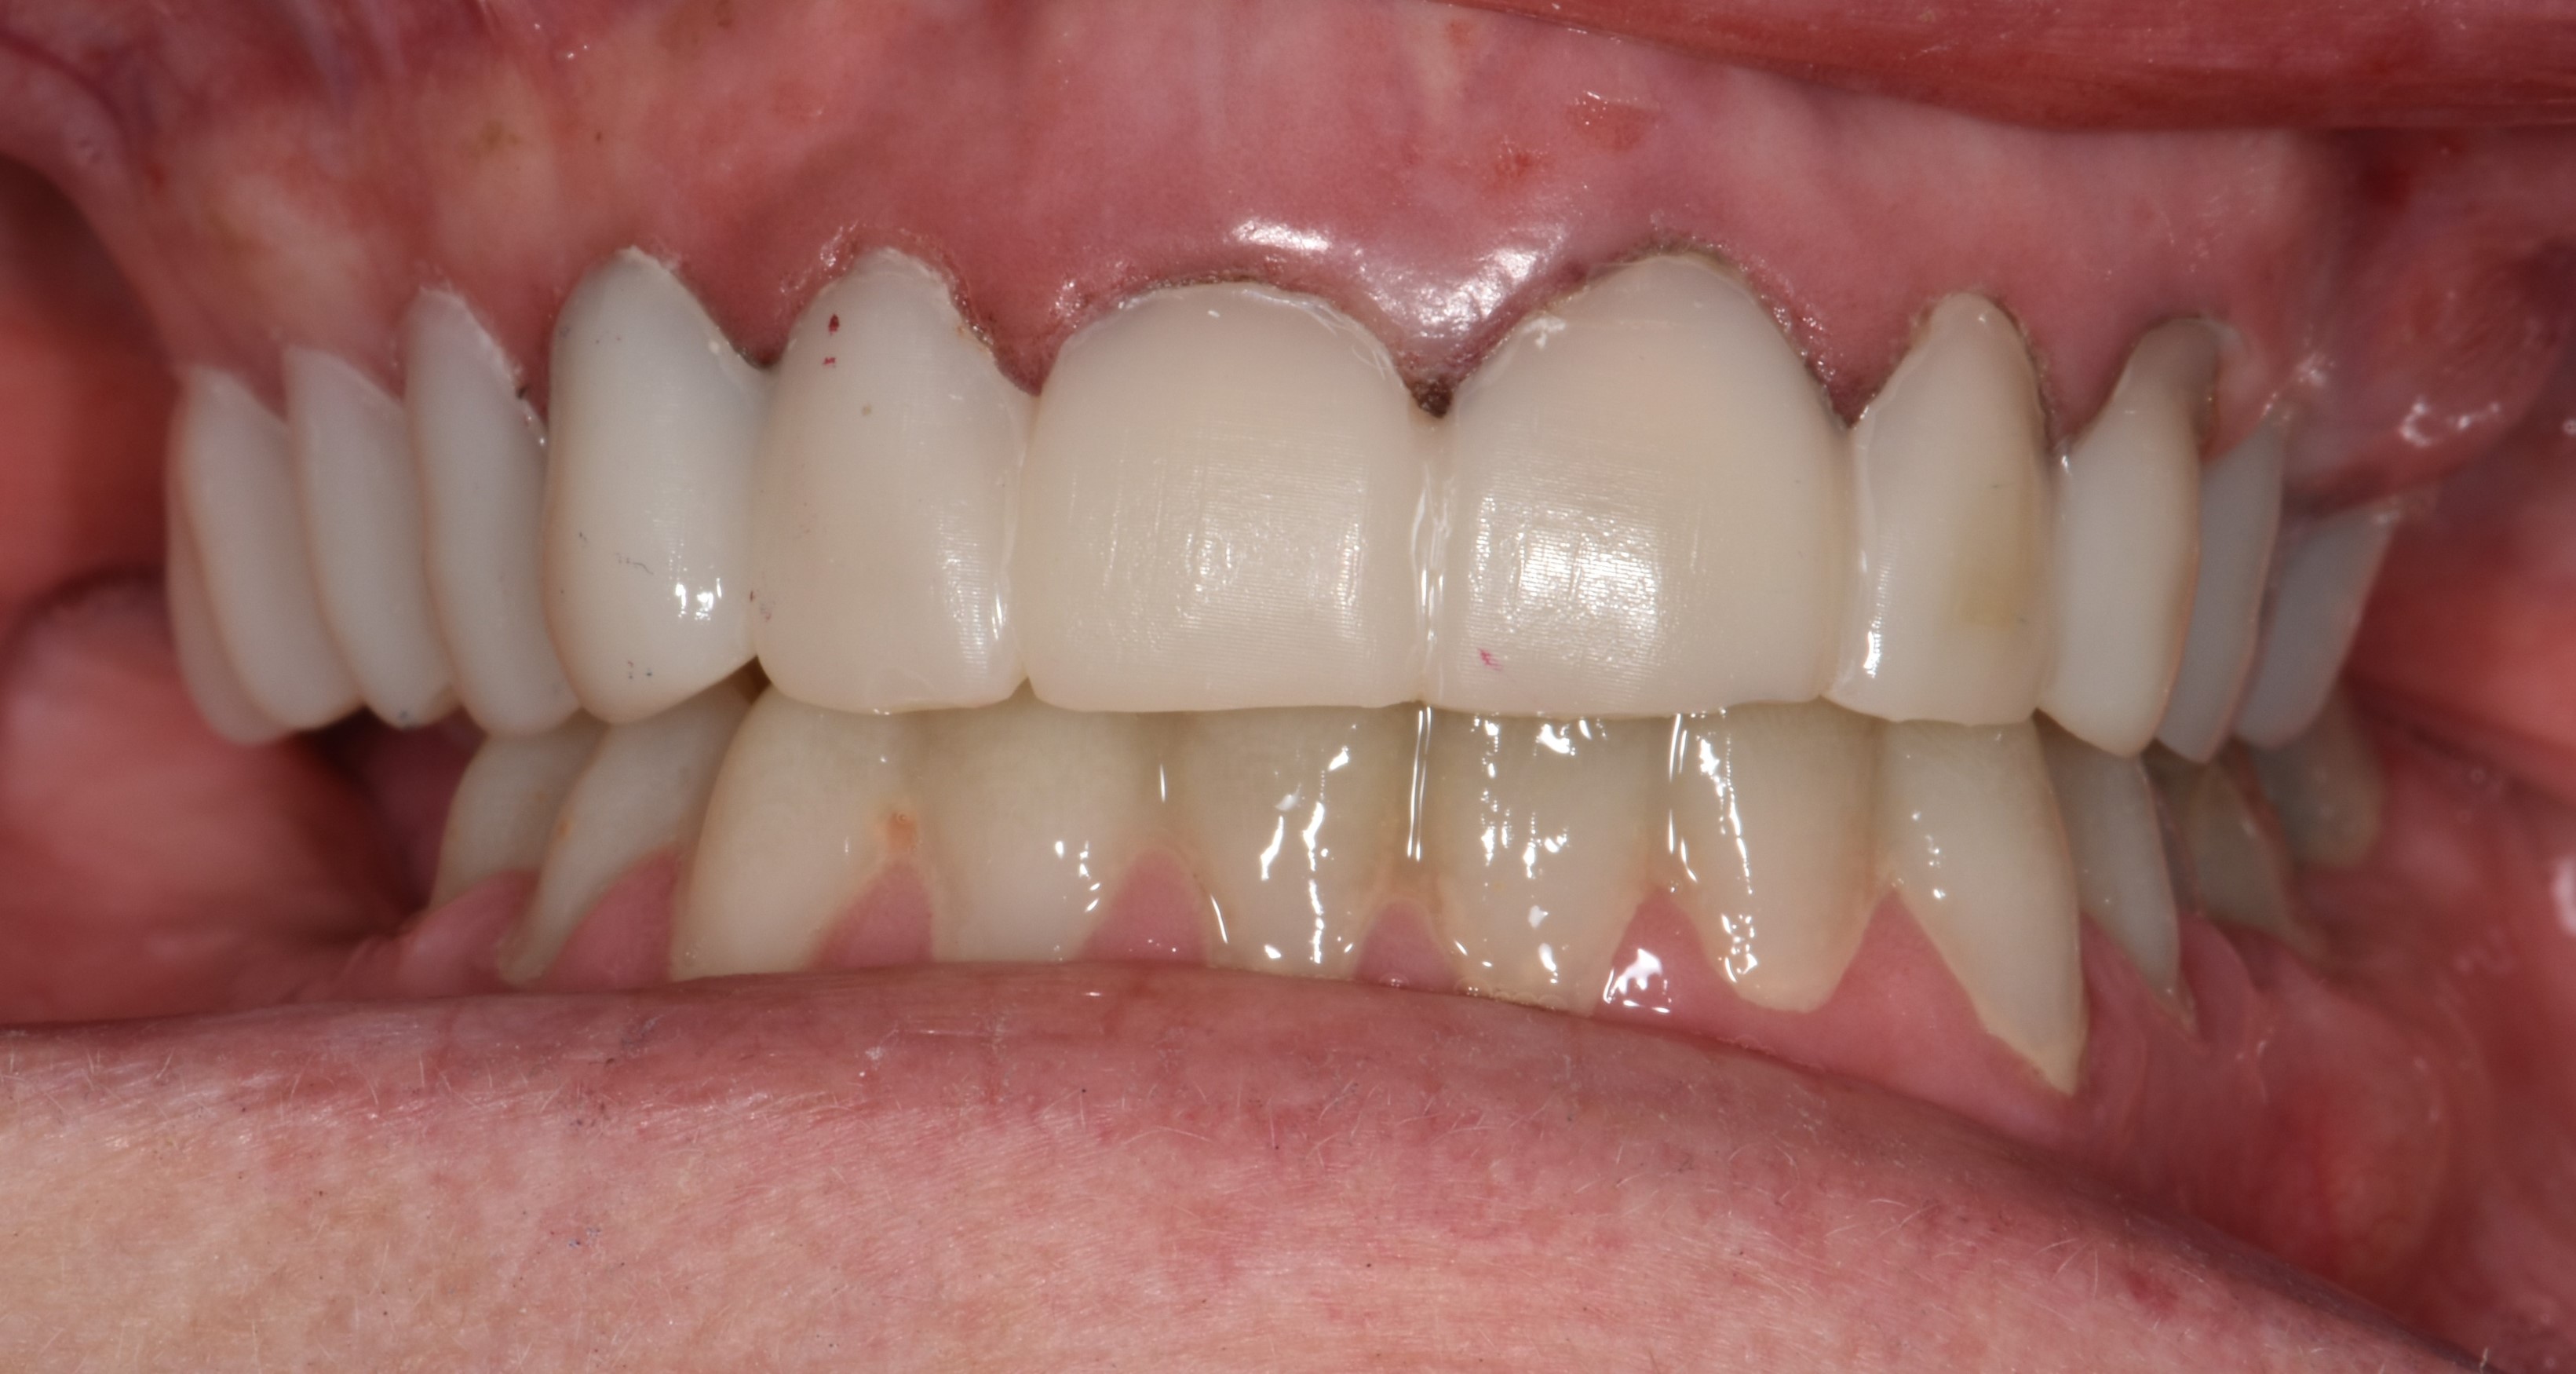

After the restorations were milled, they were sintered and polished for final effect. It was decided that these restorations should not be glazed to avoid the added abrasivity that accompanies this finish to the restoration.22 The patient was then scheduled for temporary crown removal. The final crowns were fitted on the prepared teeth, and the contacts adjusted. The patient reported that she was pleased with the feel and esthetics of the restorations, and the restorations were cemented (Figure 14 through Figure 19).

Fig. 5

Fig. 14

Fig. 15